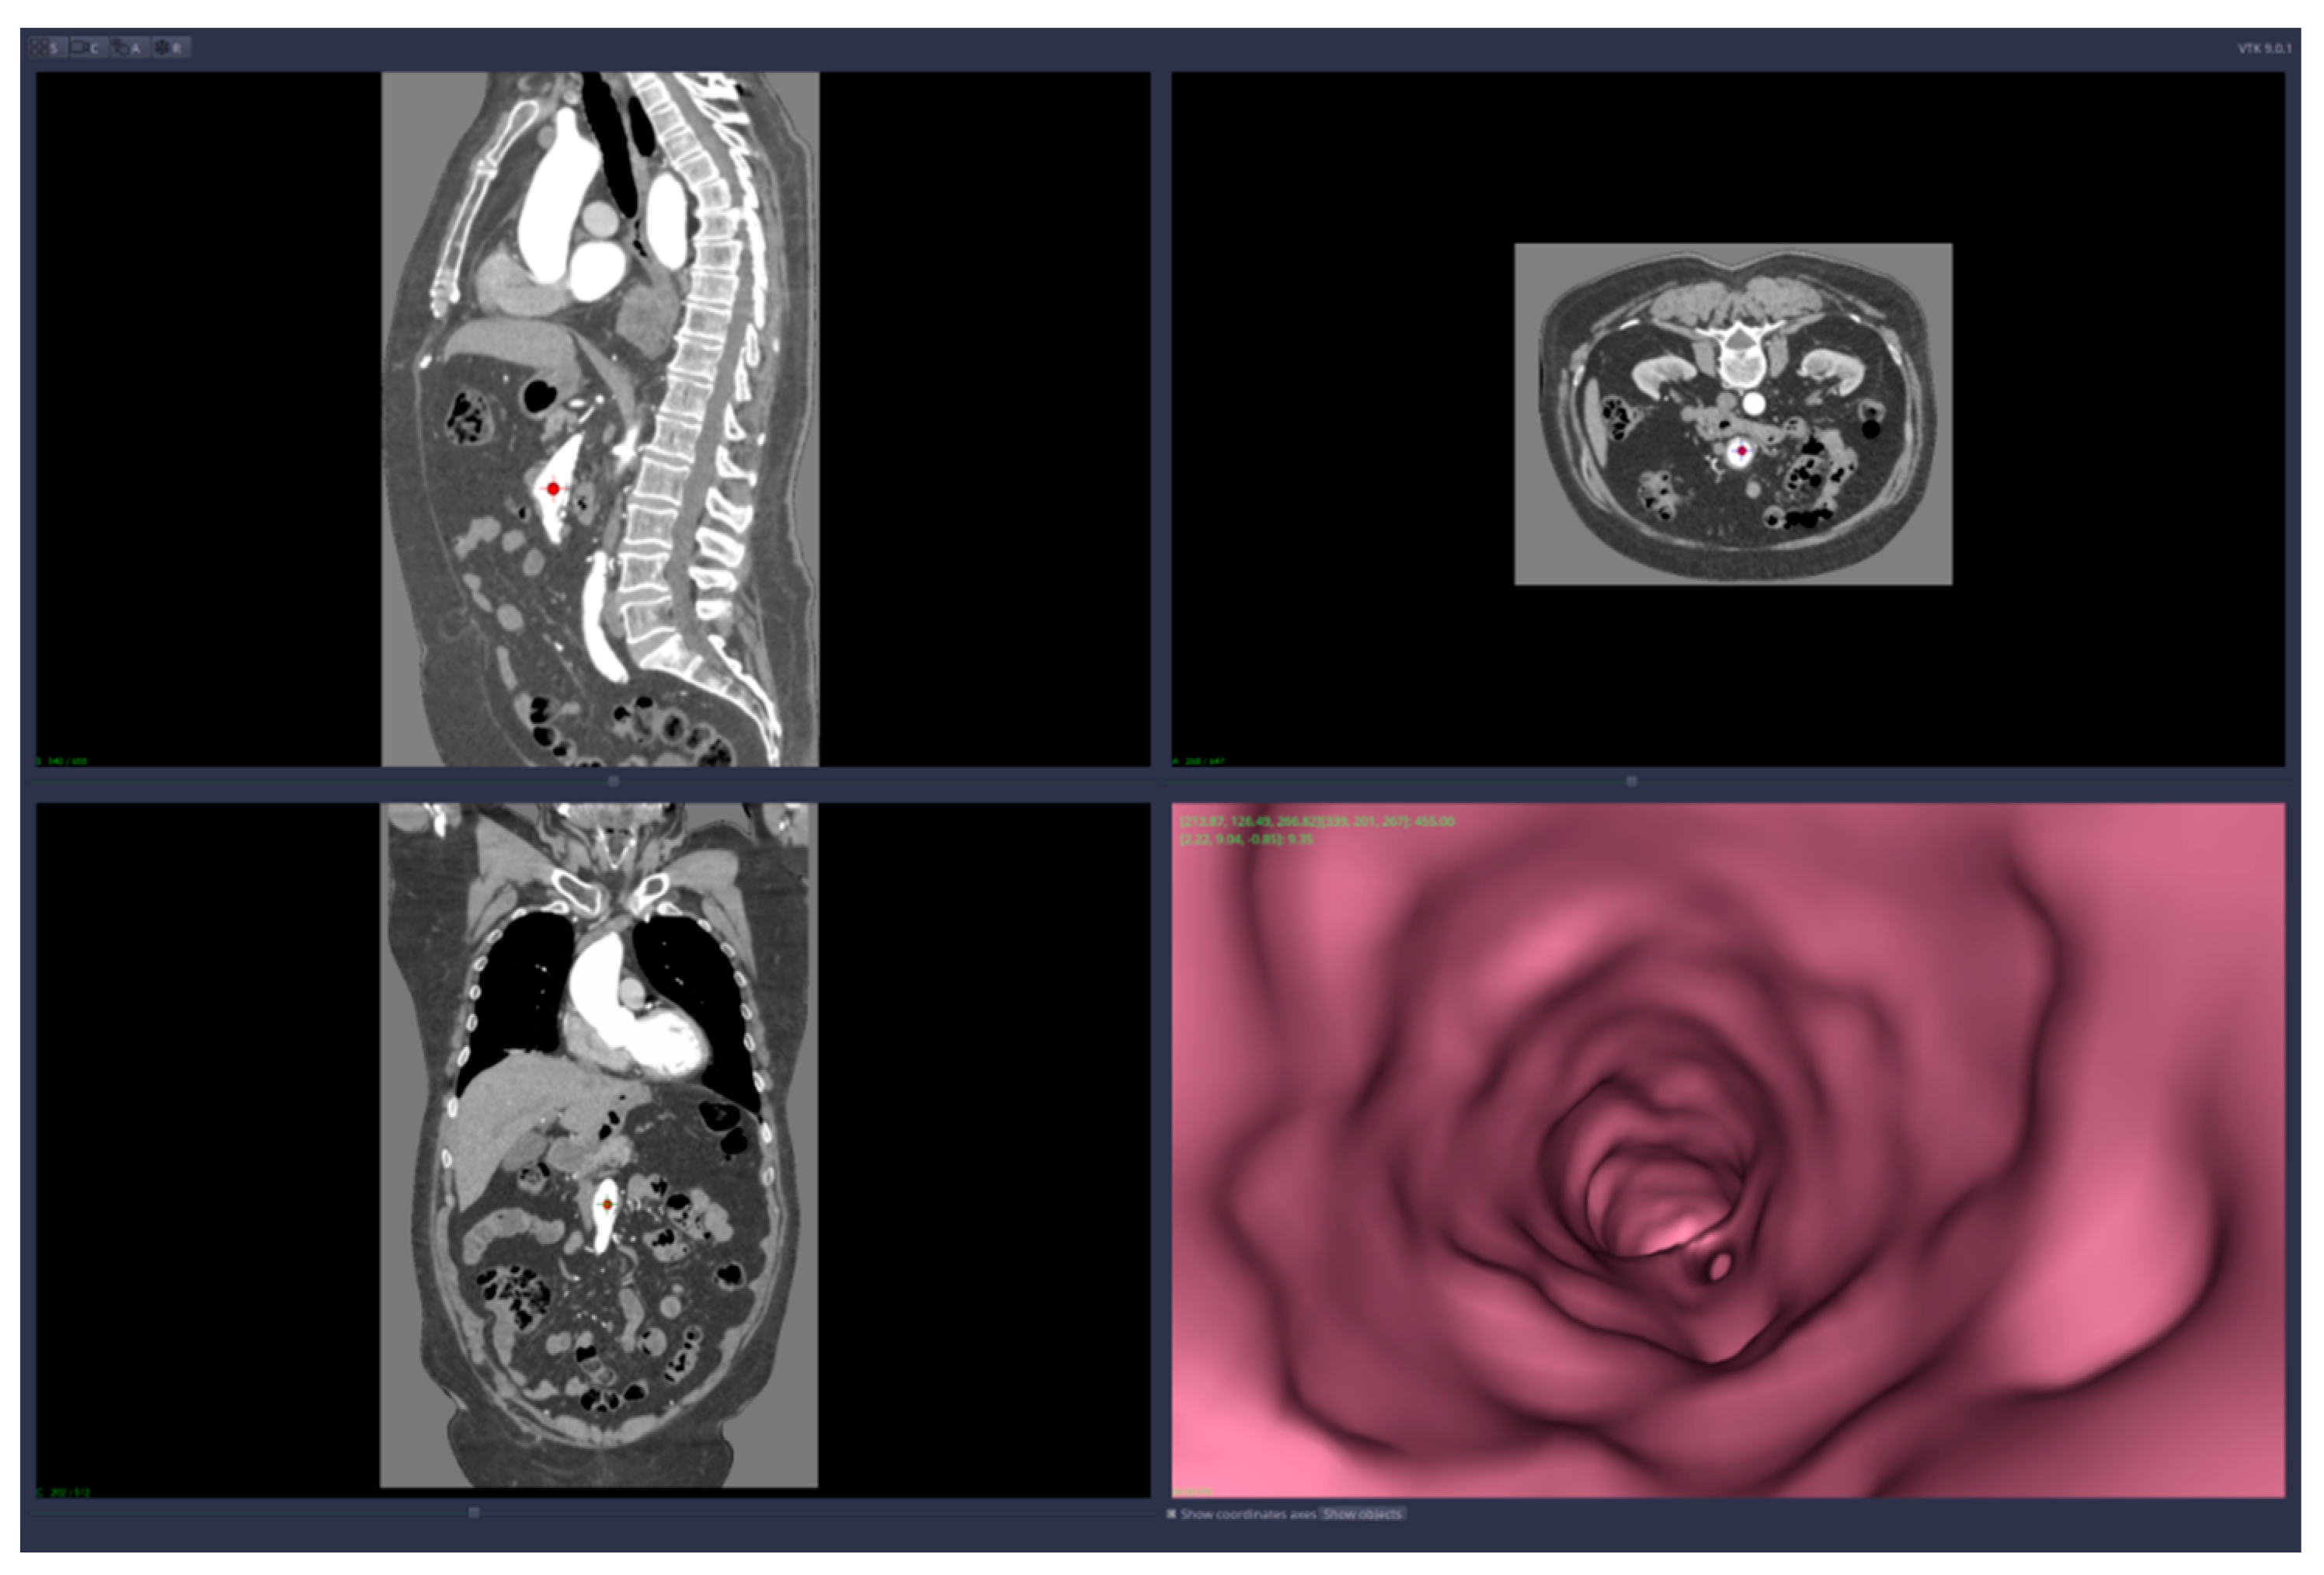

• Virtual angiography—virtual 3D navigation through the mesenteric artery and aneurysm zone (see Figure 3, Figure 4, Figure 5, Figure 6 and Figure 7)

The automatic measurements are in fact the values of the artery diameter computed automatically in points either chosen by the user or along the virtual angiography path.

As you can determine from those figures, this particular aneurysm included the whole main part of the superior mesenteric artery, was fusiform in shape and involved all small intestinal branches, which makes the cases difficult to repair.

Figure 4. Virtual angiography—inside the mesenteric artery aneurysm (direction is opposite to the blood flow).

Figure 7. Virtual angiography trajectory—“procedure” started opposite to the blood flow, bottom-up, with the final point into the aorta (direction is opposite to the blood flow).